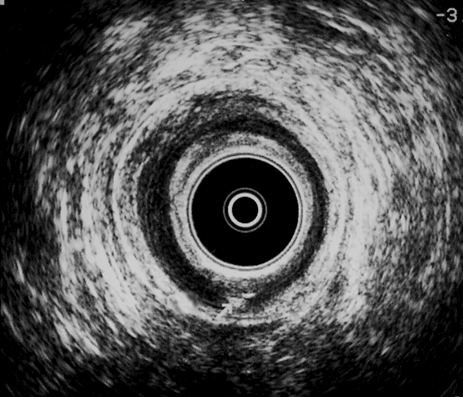

CANAL ANAL MEDIO: Con agua oxigenada se evidencia imagen hiperecoica a las 6 h a nivel submucosa, compatible con orificio interno fistuloso posterior (flecha)